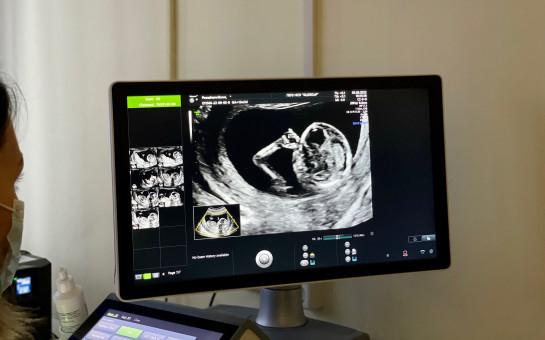

В 2024 году планируется охватить диспансеризацией 1 400 000 жителей Новосибирской области, сообщила Елена Аксенова. В этом году впервые в диспансеризацию включили исследования для оценки репродуктивного здоровья.

– Будет проводиться диспансеризация репродуктивной функции для граждан фертильного возраста – от 18 до 48 лет, отдельный план обследований для мужчин и для женщин, что позволит узнать больше именно о репродуктивной функции организма и более тщательно и благоприятно запланировать беременность, – объяснила Елена Аксенова.